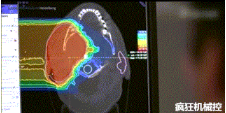

▲360°重離子治療一體機治療腫瘤

360°重離子治療一體可從任何角度用重離子(碳,氦,氧)和質子(氫)照射腫瘤。此外,基于機器人的治療臺可以通過六種方式進行調整。

光柵掃描被集成到360°重離子治療一體機中,這種極其精確的照射方法以毫米為單位掃描腫瘤,可以保護健康組織且只治療腫瘤區域。

特別是腫瘤在高度輻射敏感位置或者諸如視神經附近的復雜位置,可以通過選擇最佳射束入射角來減小這些器官的損傷。